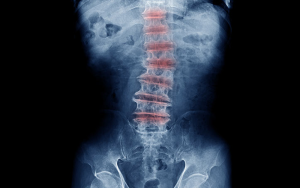

Como acontecem as Doenças Degenerativas da Coluna Vertebral?

A degeneração da coluna vertebral é uma doença progressiva, o que significa que piora com o tempo. Entenda como a doença progride:

Com o tempo, o fluido no disco de amortecimento entre a vértebra diminui, afetando a capacidade do disco de funcionar normalmente;

Fissuras podem se desenvolver no anel, a camada externa do disco, tornando-o mais suscetível aos vazamentos do conteúdo interno;

Os vasos sanguíneos vertebrais podem afinar, afetando o suprimento de sangue para o disco;

Tudo isso faz com que as articulações do lado da vértebra experimentem um aumento da carga de trabalho, contribuindo para a degeneração com o tempo!